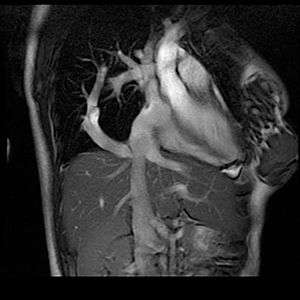

| Chest MR angiography in a patient with scimitar syndrome | |

The diagnosis is made by transthoracic or transesophageal echocardiography, angiography, and more recently by CT angiography or MR Angiography.